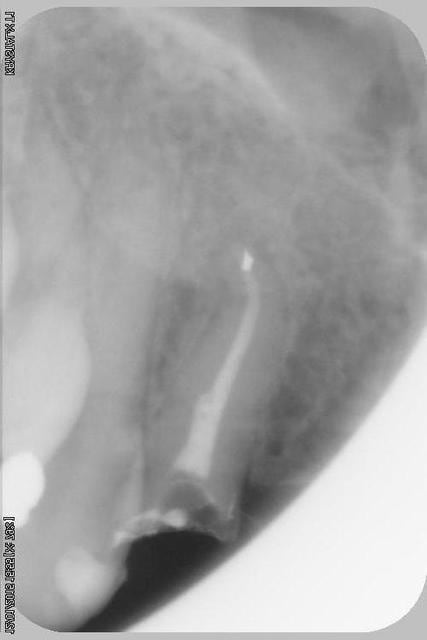

Donc dans un premier temps,je décide d'essayer de retraiter 12/22, de toute façons ça ne peut pas être pire que ce qui tiens depuis 10 ans... enfin 12 mobilité quasiment 3.

ensuite Srew post (bouh...) et résine, afin de pouvoir poser un provisoire et réfléchir à l'avenir du parodonte...car il va y avoir un problème quelle que soit la solution choisie.

013copier i9y3do - Eugenol

Img 1857r cxv5g1 - Eugenol

003copier gsgoia - Eugenol

012copier yso0mb - Eugenol

002copier mphusk - Eugenol

Sur la reprise de 22 je pense que tu as fais un beau "tout-droit" à l'apex... le canal devait suivre la courbure.

Tu es bon pour faire une chir-apicale dans quelques mois !

je pense que le tout droit existait déjà..

oup's j'ai omis la digue...

Chir apicale si on garde la dent...